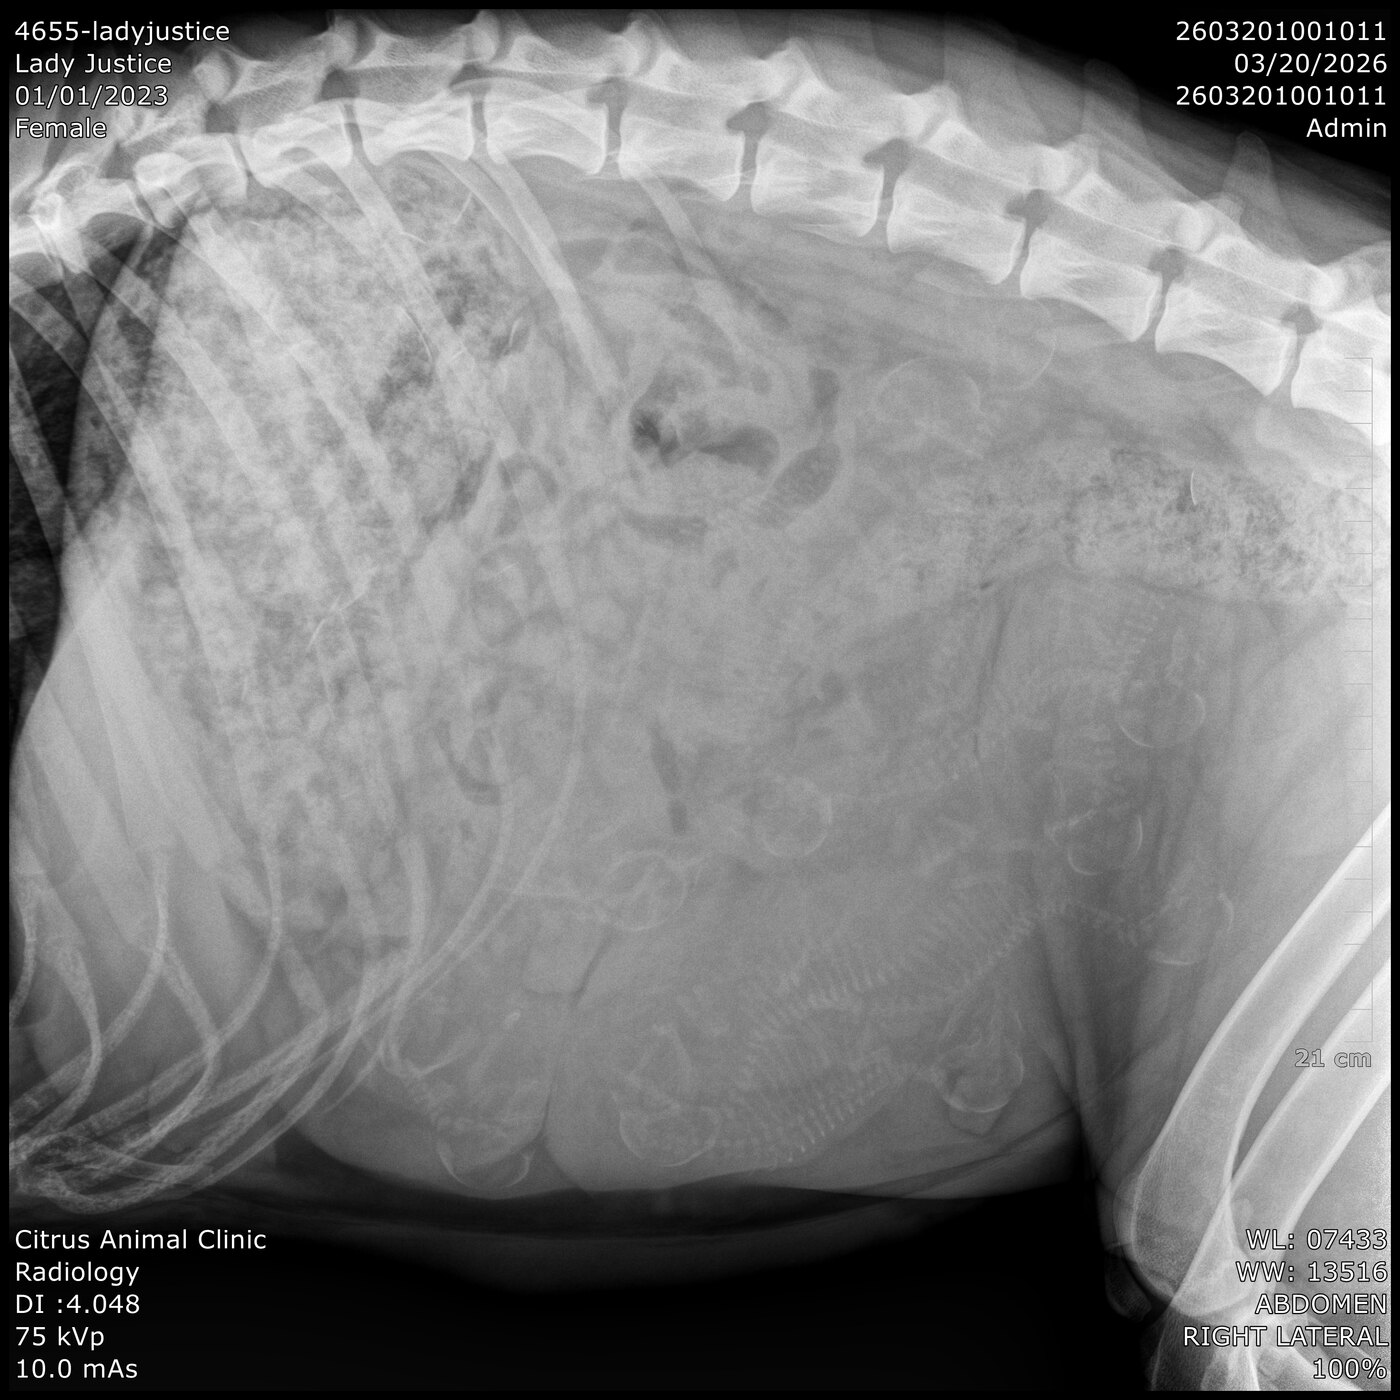

Lady Justice XVII

(Justice)

Sex:

Female

Date of Birth:

April 4th, 2023

Sire:

Kaiczar Ezekiel Zlovestny Vom Nocnihlidka

Dam:

Cora Vina-Dog Slovakia

Owner:

Mike Walker